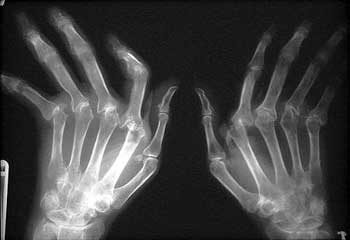

Errate combinazioni alimentari e prevalenza di cibi acidificanti alternoa l’alcalinità dei sangue e spianano la strada ai reumatismi e alle malattie al cuore nelle persone predisposte, o comunque prepara le condizioni allo sviluppo di queste malattie. Vengono colpiti più comunemente i polsi e le mani (in maniera bilaterale). I fumatori sono a rischio di sviluppare l’ artrite reumatoide , mentre quelli che consumano alcol hanno un rischio maggiore di sviluppare la gotta.

L’arma in più nelle mani di chi ha l’ artrite reumatoide si chiama alimentazione. I ricercatori del Kalinga Institute of Industrial Technology Bhubaneswar in India suggeriscono, infatti, di incorporare alcuni super cibi all’interno della propria dieta. Comunque, i migliori risultati si ottengono non attraverso una mera riduzione dei carboidrati , ma attraverso una riduzione generale dei regime alimentare, in quanto i carboidrati non sono gli unici colpevoli. ARTROSI E ARTRITE REMAUTOIDE Artrosi e artrite remautoide causano una degradazione della cartilagine delle articolazioni. Quando si parla di artrosi e di artrite remautoide, si tende a fare confusione tra le due malattie, perché entrambe coinvolgono le articolazioni delle ossa, registrando un decorso invalidante e progressivo similare.

L’ artrite è l’infiammazione di una o più articolazioni che può provocare rossore, gonfiore, dolore e, a volte, perdita di mobilità articolare. L’azione indiretta si riferisce al compito del cortisolo di contrastare tutte quelle patologie promosse dall’assunzione dei carboidrati : l’infiammazione cronica, l’infiammazione intestinale (Sibo), le malattie autoimmuni (ad esempio artrite reumatoide ), infiammazione causata dal tessuto grasso (morte degli adipociti). Ecco quali alimenti possono aiutare a prevenire e ridurre i sintomi di artrite e quali, invece, possono peggiorare lo stato infiammatorio del corpo. Una dieta sana,pochi grassi e colesterolo è il punto di partenza per combattere patologie complesse, come l’ artrite reumatoide , o problemi molto diffusi, come l’artrosi. Le più recenti raccomandazioni (referenze) per ridurre i dolori legati all’ artrite reumatoide e per migliorare il funzionamento del sistema immunitario, si traducono in obiettivi nutrizionali che devono essere raggiunti giorno dopo giorno, per indurre dei cambiamenti positivi e duraturi.

Accomunate da dolori muscoloscheletrici, al punto da rappresentare la prima causa di disabilità nel nostro Paese, queste malattie sono in parte di origine autoimmunitaria, come l’ artrite reumatoide o la sclerodermia. Le manifestazioni più comuni, però, sono dovute ad artrosi e artriti: in Italia ne soffrono almeno milioni di persone. Si manifesta con una forma di infiammazione più o meno acuta, Colpisce in prevalenza le donne e talvolta si presenta già in età giovanile, per poi peggiorare nel corso del tempo.